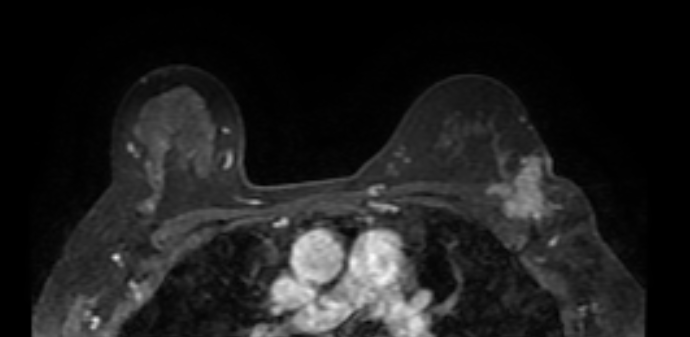

36 year old female comes with history of left breast lump. She is evaluated outside for same and HPR is papillary lesion. She comes to our hospital, we repeat her mammogram and USG, which is suggestive of a high density large mass with lobular margin in upper outer quadrant of left breast. As out side HPR is discordant with imaging finding, we repeat her biopsy and MRI. Repeat biopsy is suggestive of again papillary lesion. And MRI is suggestive of invasion of chest wall muscle. What do we do now?

Adenomyoepithelioma is a primary breast neoplasm of rare entity caused by proliferation of both epithelial and myoepithelial components, Benign to low grade malignant behavior and has a propensity for recurrence. Either epithelial or myoepithelial component can show malignant transformation so thorough evaluation recommended*. Overlap of histopathological features usually lead to misinterpretation as invasive carcinoma or intraductal papilloma or sclerosing adenosis. Complete wide excision with negative margins is standard treatment to prevent local recurrence. It is difficult to diagnose this on imaging alone, however familiarity with this rare entity to radiologist is essential to raise possibility.

Final histopathology was suggestive of Adenomyoepithelioma (AME). (Few foci of atypia were seen, however there was no malignancy)